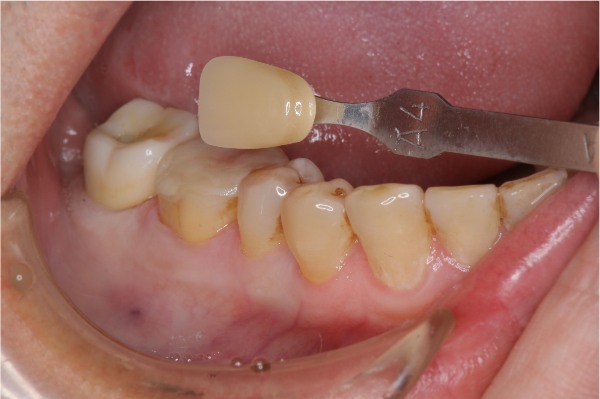

照相比色